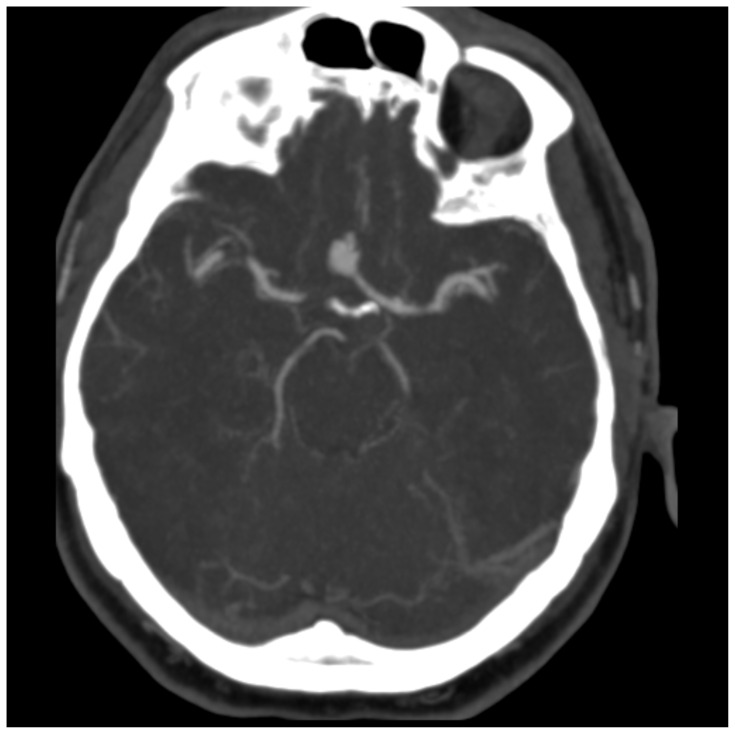

Introduction: Headache is the fifth most common chief complaint in the emergency room, and the vast majority are ultimately diagnosed as benign primary headaches.1,2 However, subarachnoid hemorrhage (SAH) is one of several critical diagnoses which can present as a headache. With a case fatality rate of up to 66.7% in some instances, SAH is considered a "can't miss" diagnosis.3Subarachnoid hemorrhage is classically associated with a thunderclap headache, one definition of which is a headache that reaches maximal intensity within one minute or less and reaches a seven out of ten in severity.1 Unfortunately, a thunderclap headache is not as sensitive nor specific for SAH as is often taught. In one study, only 50% of patients with an aneurysmal subarachnoid hemorrhage presented with a thunderclap headache and an additional 19% of SAH headache came on more gradually over the course of five minutes.4 A second study found that only 66% of SAH patients reported a thunderclap headache.2 Thunderclap headaches can also be associated with other intercranial pathology including intracerebral hemorrhage, cerebral venous thrombosis, cervical artery dissection, posterior reversible encephalopathy syndrome, meningitis, and temporal arteritis among others.1,2 In a large observational study, SAH accounted for 32% of the serious pathology cases identified in patients with a thunderclap headache. Even among the thunderclap headache cohort, however, 88% of patients ultimately had a benign diagnosis (compared to 93% of patients who did not report a thunderclap headache).2Additional signs and symptoms of SAH include seizures in 6-9% of patients, vomiting, neck pain and stiffness, visual disturbances, loss of consciousness, and focal cranial nerve or supratentorial deficits.1,5 A non-contrasted computer tomography (CT) of the head within six hours of headache onset can have a sensitivity of 98.7 to 100%; however, the sensitivity decreased to 86% at the 24-48 hour mark.1,6 A meta-analysis found a pooled six hour sensitivity of 1.0 and asserts that a head CT interpreted as negative by an attending radiologist effectively rules out SAH in neurologically intact patients with a defined onset of a thunderclap headache.6 Some guidelines in the United States still recommend shared decision making with the patient to choose between a Lumbar Puncture (LP), Computer Tomography Angiogram (CTA), or no further testing to rule out SAH in the case of a negative head CT.2 The more time that has elapsed between onset and CT imaging, the stronger the recommendation to pursue further testing. A negative head CT followed by a negative LP approaches 100% sensitivity for ruling out SAH, and a negative head CT with a negative CTA has a 99.4% probability of ruling out SAH.1,3 Thus it is an important learning point that if a headache has been ongoing for more than six hours and there is a high pre-test probability for an SAH, a negative head CT is not sufficient to rule out the diagnosis, and a secondary test should be ordered.Status epilepticus is defined as five minutes of continuous seizure activity or repeated seizures without return to baseline between seizures.7 The immediate priorities for a seizing patient include providing supplemental oxygen, considering intubation if patient is unable to protect airway, obtaining IV access if not previously established, and checking glucose.7 The main priority for a patient in status epilepticus is to stop the seizure with seizure abortive medications, typically benzodiazepines, and treat life-threatening causes of status epilepticus.7 This simulation will enable learners to diagnose SAH that is not the classical "worst headache of my life" and manage an actively seizing patient.

Educational objectives: At the conclusion of the simulation leaners will be able to:Efficiently take a history from the patient and perform a physical exam (including a complete neurological exam)Identify red flag symptoms in a patient complaining of a headacheOrder and interpret the results of a CT of the head and either a CT angiogram of the brain or a lumbar puncture to make the diagnosis of subarachnoid hemorrhageDemonstrate appropriate management of a seizureCheck a fingerstick glucoseProvide supplemental oxygenAdminister an IV or IM benzodiazepine to treat the seizureUtilize the I-PASS framework to communicate with the inpatient team during the transition of care.